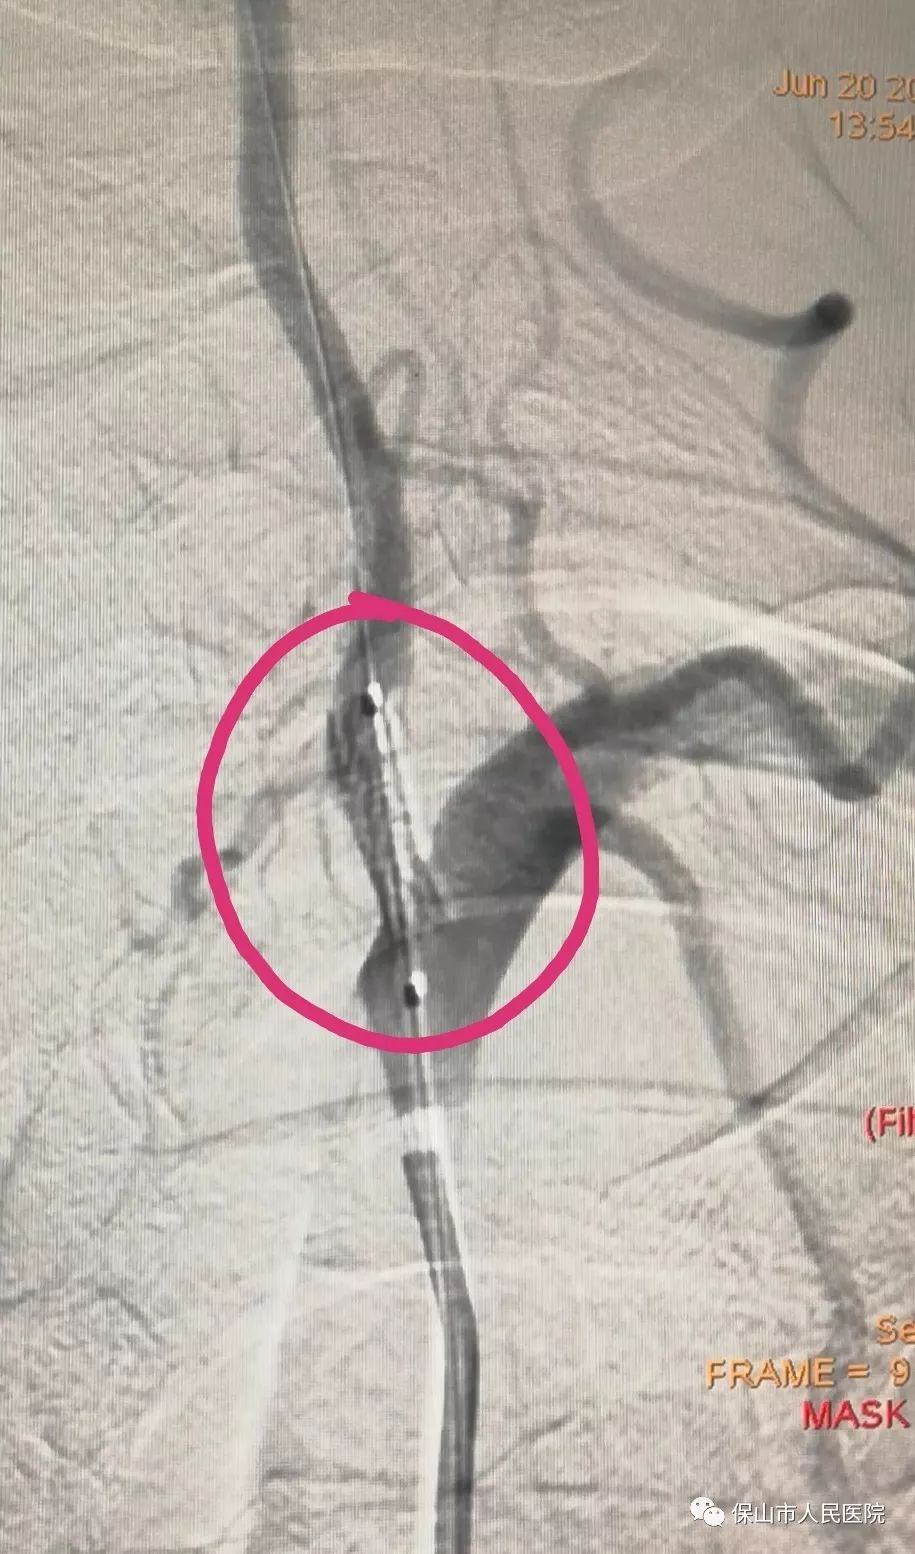

支架釋放之後,再次造影,對比前麵的視頻,很直觀的改變,狹窄部位已經被支架支撐開來,椎動脈裏麵的血流速度比之前加快不少。

另外一名患者情況相似,術中造影診斷為(wei) 右側(ce) 椎動脈開口狹窄,狹窄程度約70%,確定位置後,支架到位釋放。

支架植入前後對比,右側(ce) 椎動脈的狹窄部位也已經被支架撐開,椎動脈狹窄問題解決(jue) 。